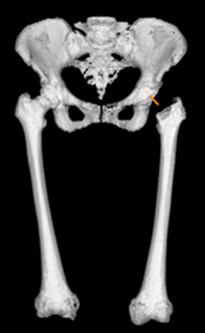

- 人工股関節全置換術(THA)を行う際、インプラント同士のインピンジメント(I-I imp)を生じない手術を心掛けている

- I-I impは脱臼や破損などの主要因 (Shon et al. 2005)

- 3次元術前計画ソフトZedHipはTHAにおける術前後で可動域シミュレーション(ROM sim)が可能なソフトである

ZedHipの普及によりTHAにおけるインピンジメントの可視化が容易になった

ZedHipとHipCOMPASS® (LEXI Co., Ltd., Japan)を用いてI-I impフリーをめざし術前計画・術中支援・術後評価を行ったTHAを紹介する

【当院でのTHA】

| アプローチ | MIS-ALS |

| 使用機種 | BiCONTACT total hip system ® (エースクラップ社) 32mm head oscillation angle (144度) |

| 術前計画 | ZedHip |

| 術中支援 | HipCOMPASS ®を用いてカップを設置 |

| 術中確認 | インピンジメントの有無を確認![]() |

| 術後評価 | ZedHip |

| 後療法 | 荷重・動作制限なく翌日より離床 1週間退院のクリニカルパス |